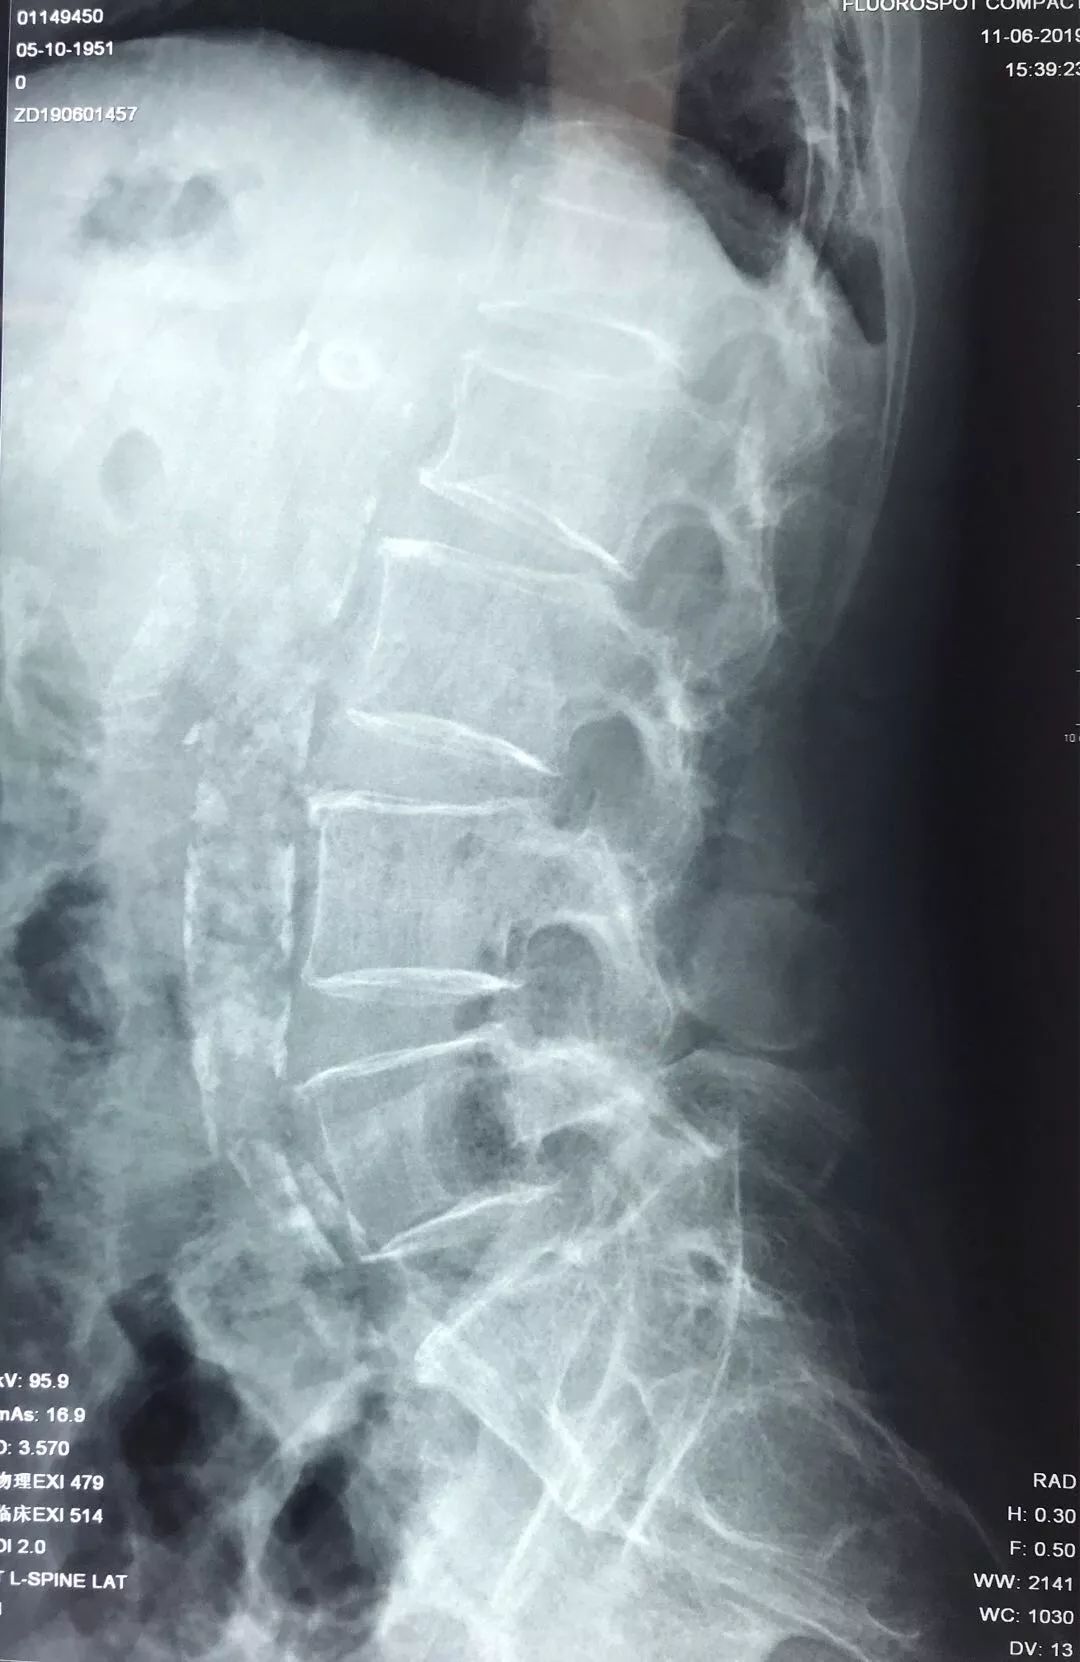

术前检查